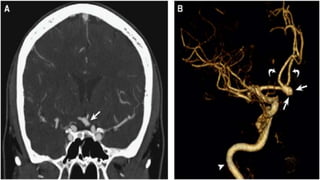

INVESTIGATIONS

• CT angiogram

INVESTIGATIONS • CT scan •CT angiogram • MRI and MRA • DSA